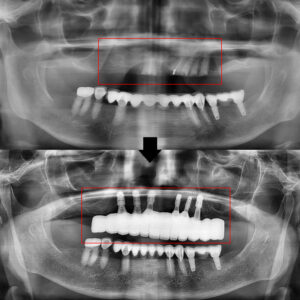

내부의 자세한 상황을 알기 위해

파노라마 사진을 찍어보았습니다.

파노라마를 확인해 보니,

위쪽의 아직 발치되지 않은

잔존치근(뿌리)가 있었습니다.

환자분께서는 기존 틀니를

오래 사용하면서 헐거움과 통증 등으로

불편함을 지속적으로 호소하셨고,

더 이상 임시방편이 아닌

근본적인 해결을 원하셨습니다.

이에 병점치과 365서울차오름에서는

전체적인 저작 기능 회복과

안정적인 고정을 위해

잔존치근을 전부 발치한 후

All-on-6 임플란트 치료를

계획하게 되었습니다.